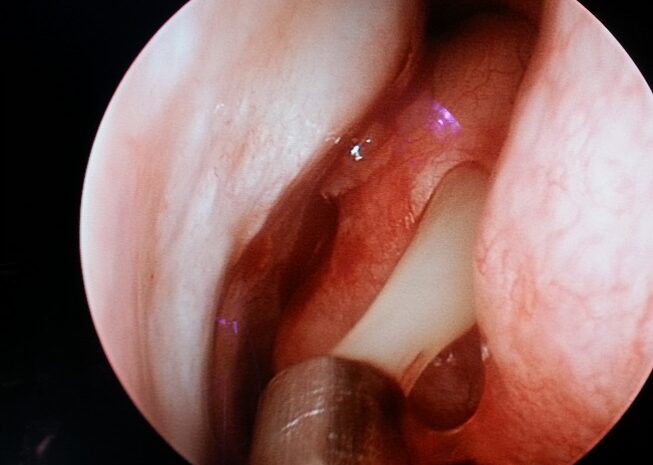

Endoskopik sinüs cerrahisi 1970’li yıllarda tanımlanmış ve kısa sürede yaygınlaşmıştır. Bu cerrahi yöntem fizyolojiye uygun olması sebebi ile çok etkili olmuş ve kronik sinüzitin tedavi yaklaşımını tamamen değiştirmiştir. Bu sebeple sinüzit tedavisinde kullanılan eski cerrahi yöntemlerin hemen hepsi kısa sürede terk edilmiştir. Bu cerrahi yaklaşımda temel mantık minik kamera uçları ile burun içini görüntüleyerek, sinüslerin tıkanmış olan doğal kapılarını açıp genişletmek, osteitli dokuyu çıkarırken, kemik yapıları kaplayan mukozayı mümkün olduğu kadar korumaya dayanmaktadır. Sinüs mukozaları korunduğu için zaman içinde mukus taşınması fonksiyonu yeniden başlar ve normal fiyolojik döngü elde edilebilir. Özellikle anatomik bozukluklara bağlı kronik sinüzit sorunu böylece tamamen ortadan kaldırılabilir ve bu hastalarda kronik sinüzit tekrarlamaz.

Endoskopik sinüs cerrahisinde ameliyat tamamen burun içinden yapılır. Cilde ve kemik dokulara kesi yapılmaz. Gereksiz doku çıkarılmaz ve bu nedenle ameliyat sonrası iyileşme daha kısa sürede ortaya çıkar. Burun içinin çok net bir görüntüsü büyütülerek monitora aktarıldığı için göz ve beyin ile ilgili komplikasyonlardan uzak durmak mümkün olur. Ameliyat burun ve sinüslerin fizyolojisine uygun olduğu için kronik sinüzitin tekrarlama ihtimali çok düşüktür.